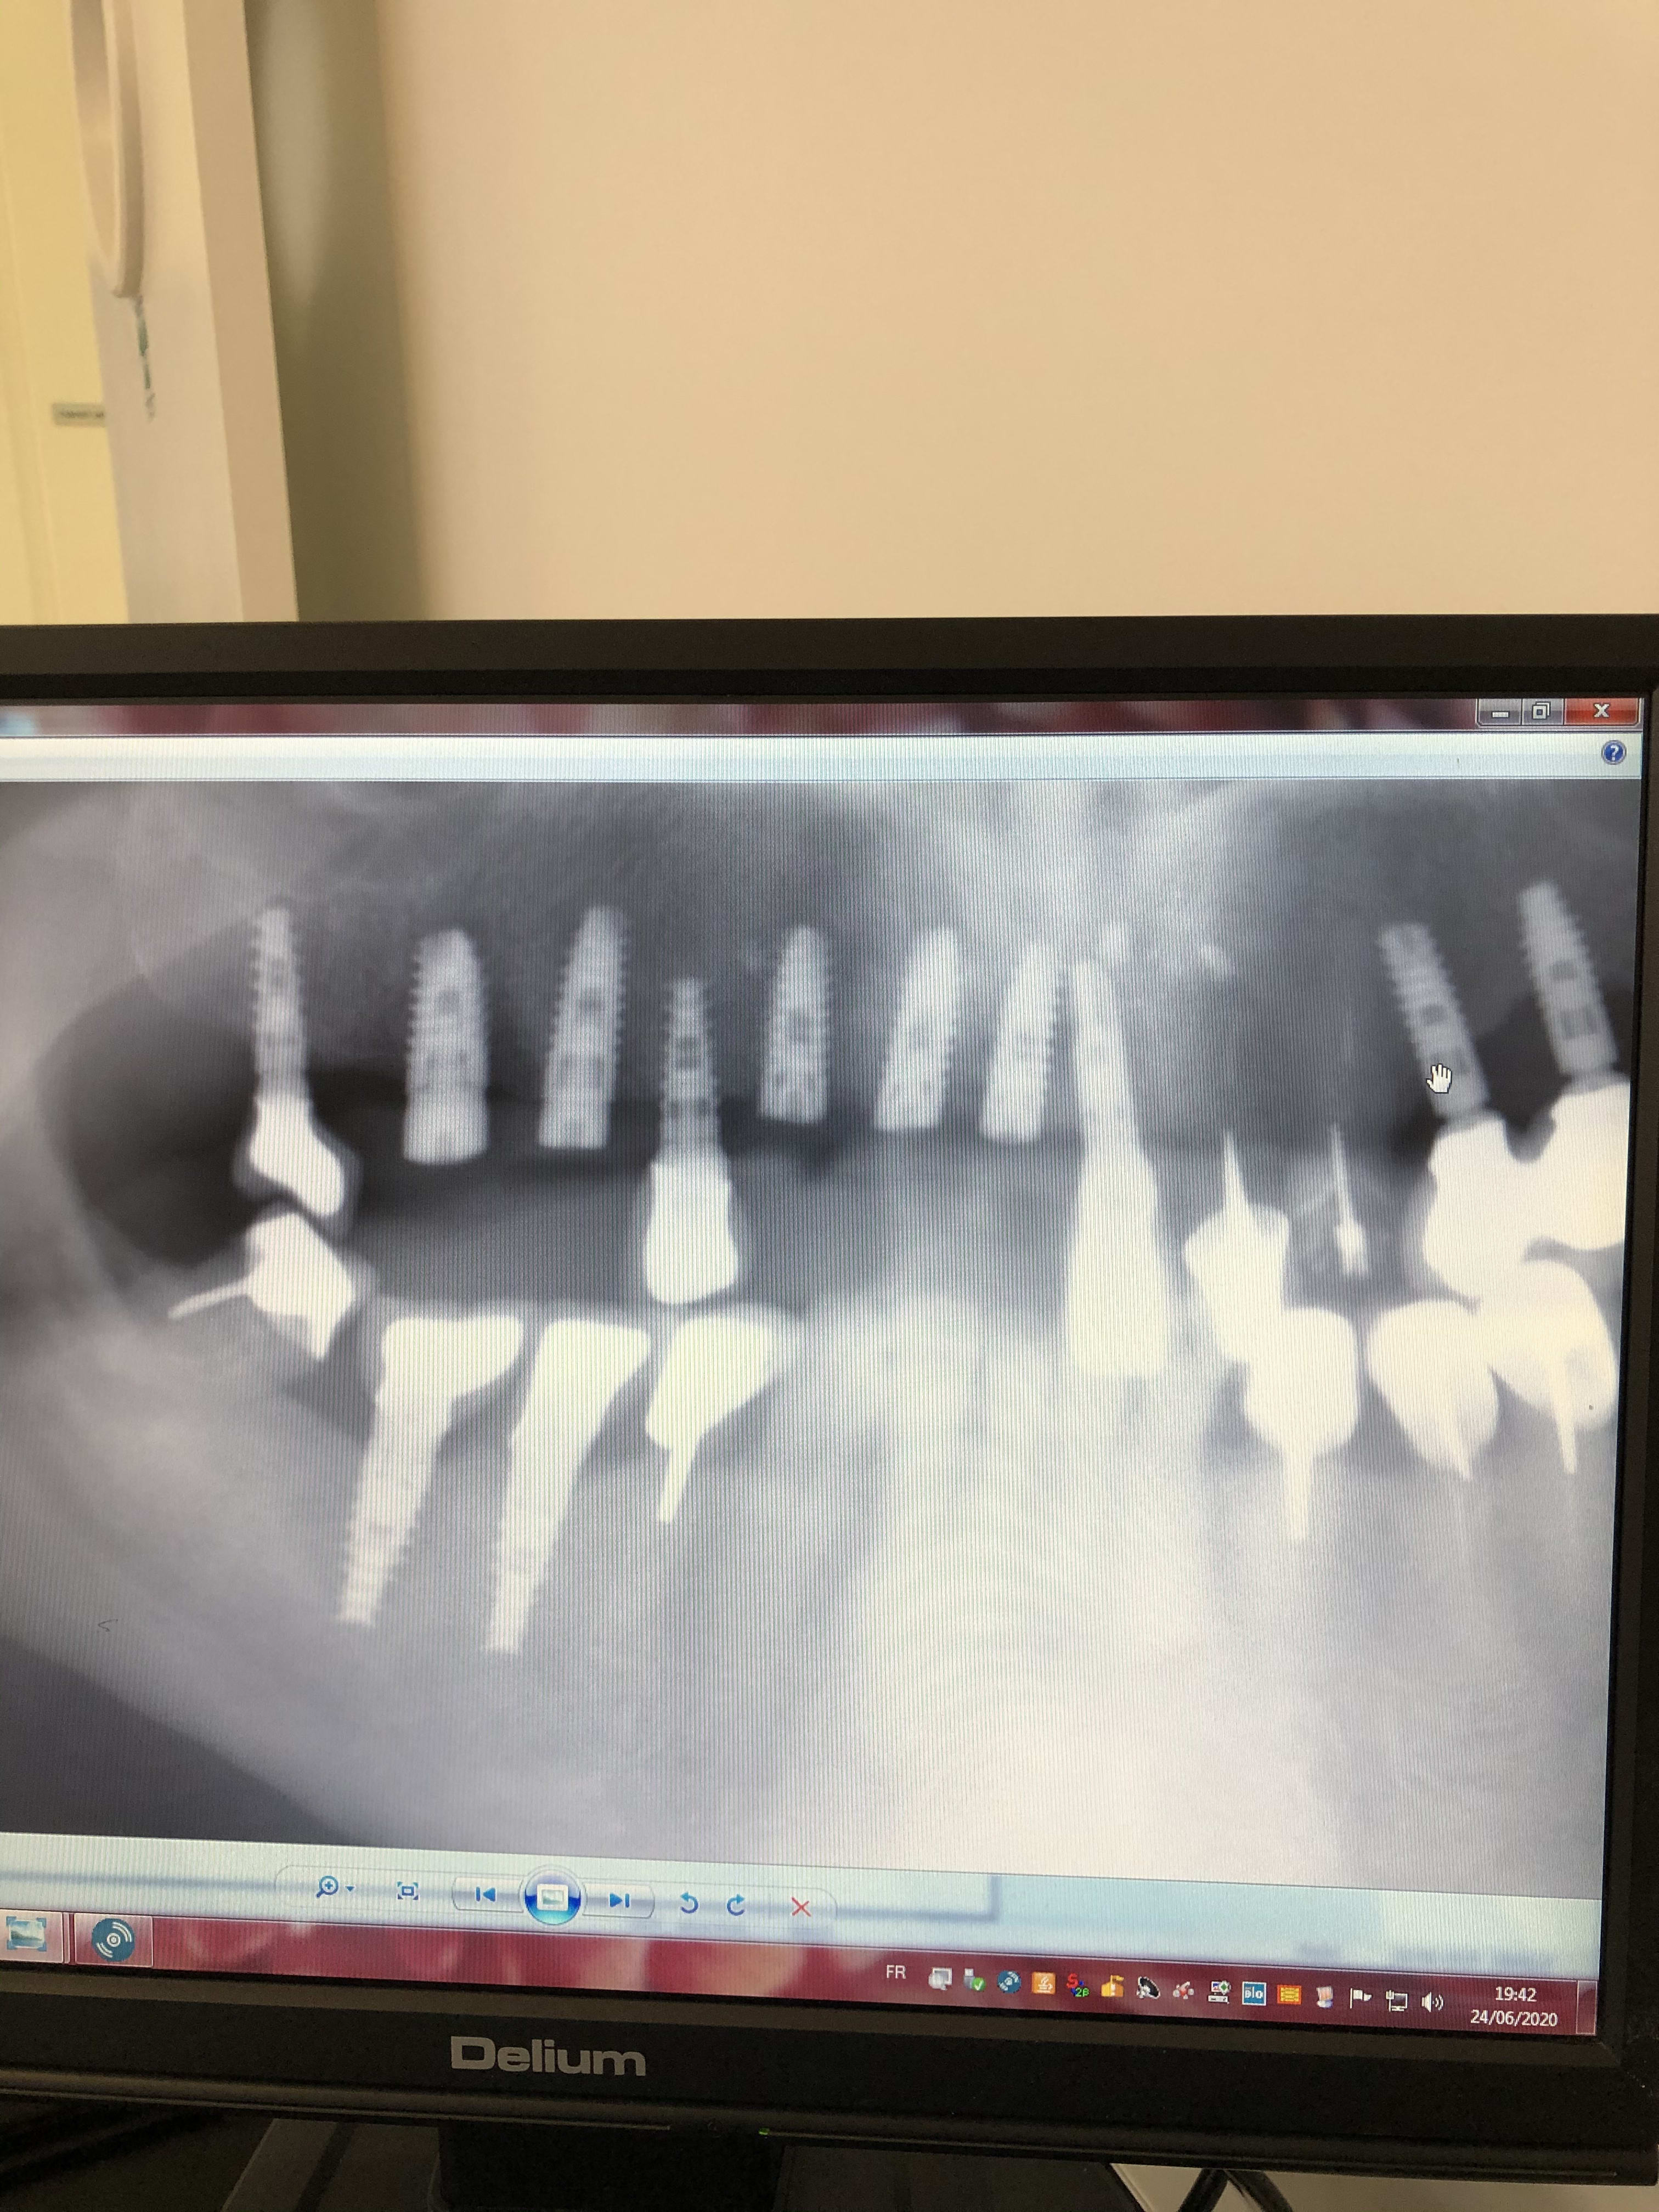

Bonjour j ai posé plusieurs implants 5 au maxillaire 11.12.13.15.16 le samedi 20/11 je pensais initialement que l implant 11 touchait l implant 21 déjà posé par un autre confrère mais une pano montre que ce n est pas le cas

Le pb est que le patient a l air de souffrir beaucoup malgré ibuprofens ab etc

Est il possible à votre avis que j ai tapé le canal nasopalatin et que ce serait cela (compression d un nerf?)qui lui donnerait les douleurs ou bien il faut patienter

Ci joint panos